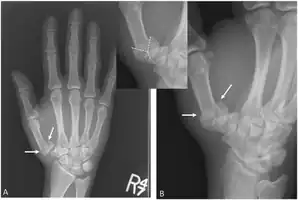

Rolando fracture - a comminuted intra-articular fracture of the first metacarpal bone.

The cause is generally a force along the long axis of the thumb, such as during a fight.[3][4] Diagnosis is by medical imaging; such as X-ray, CT scan, or MRI.[3] It results in at least three bone fragments, which often form a T- or Y-shaped pattern.[3][4] It differs from a Bennett fracture which only results in two bone fragments.[4]

There are several proposed methods of treatment. The quality of reduction does not correlate with late symptoms and osteoarthritic changes. Despite this fact, the joint surface should be restored as close to its anatomical position as possible. Some advocate fixation with Kirschner wires, or plate and screw constructions. Another accepted treatment is an external fixator accompanied by the tension band wiring technique.[8]